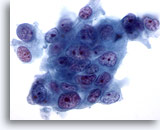

画像 2: 肝FNA – 良性肝細胞

反応性変化を来した良性肝細胞の集塊。細胞境界が明瞭な立方形の細胞が認められます。不透明な細胞質には空胞が認められるものもあれば、幾分顆粒状を呈するものもみられます。辺縁部は擦り切れた状態を呈しています。核はわずかに大小不同で、二核を有する細胞も認められます。小型の核小体がみられます。

40倍

画像 2

肝FNA – 良性肝細胞

反応性変化を来した良性肝細胞の集塊。細胞境界が明瞭な立方形の細胞が認められます。不透明な細胞質には空胞が認められるものもあれば、幾分顆粒状を呈するものもみられます。辺縁部は擦り切れた状態を呈しています。核はわずかに大小不同で、二核を有する細胞も認められます。小型の核小体がみられます。

40倍